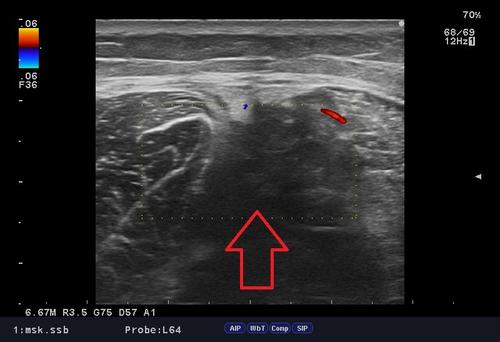

半腱様筋肉離れ.jpg

「肉ばなれ」はダッシュ時、踏み込み時など、急激に筋肉が収縮する時に、逆の伸張作用(のびる作用)が加わり、筋繊維の一部が切れたり、完全に切れたりすることです。

肉ばなれが発生した時には「バットで叩かれた」「後ろから蹴られた」などと言われる方が多く、「ブチッ」っと大きな衝撃を感じる場合が多々あります。

肉ばなれの原因としては筋疲労・柔軟性の低下・ウォーミングアップ不足が素因となっている場合が多いです。

当院ではしっかり問診、触診、視診、エコー検査を行い、「なぜ今の不調・症状が出ているのか」という、"根本的な原因"を追求し施術を行っております。